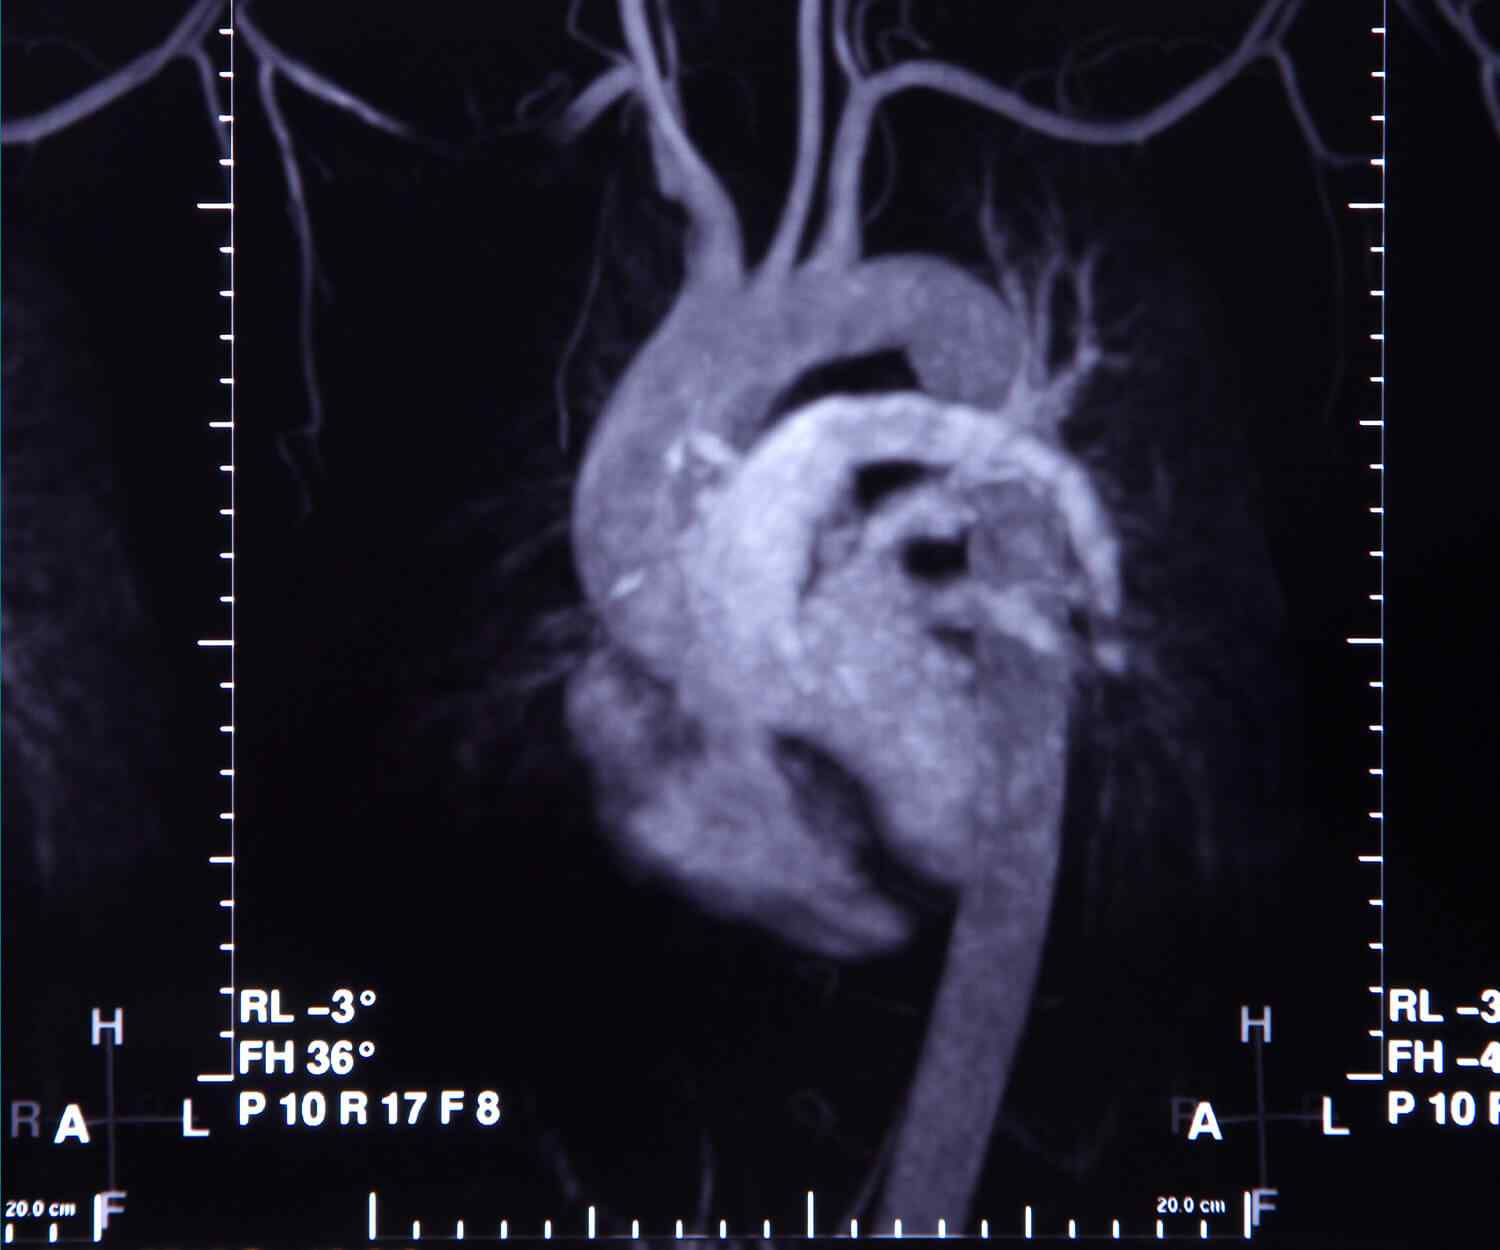

If you have known coronary artery disease, your doctor might recommend the traditional approach because you can also receive treatment during the procedure. Your doctor should give you instructions about how to prepare for CT.